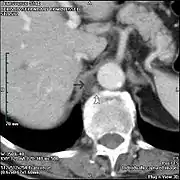

Cisterna chyli is the white bulb in the center near the bottom.

In humans, the cisterna chyli is located posterior to the abdominal aorta on the anterior aspect of the bodies of the first and second lumbar vertebrae (L1 and L2). There it forms the beginning of the primary lymph vessel, the thoracic duct, which transports lymph and chyle from the abdomen via the aortic opening of the diaphragm up to the junction of left subclavian vein and internal jugular veins.[1]